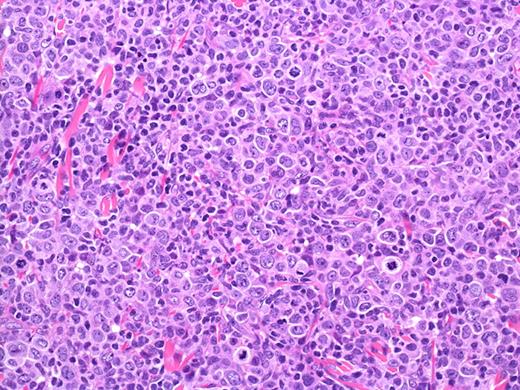

PCALCL: Cohesive sheets of anaplastic lymphoid cells H&E, original magnification ×200). The histologic photomicrograph was captured using a digital camera (AxioCam MRc5; Zeiss) mounted on an Olympus microscope (BX45; Olympus). Objective lens: 400×/0.75 NA. Imaging software: Axio Vision Release 4.8.2 (Zeiss) and Adobe Photoshop Version 8.0 (Adobe Systems Inc).